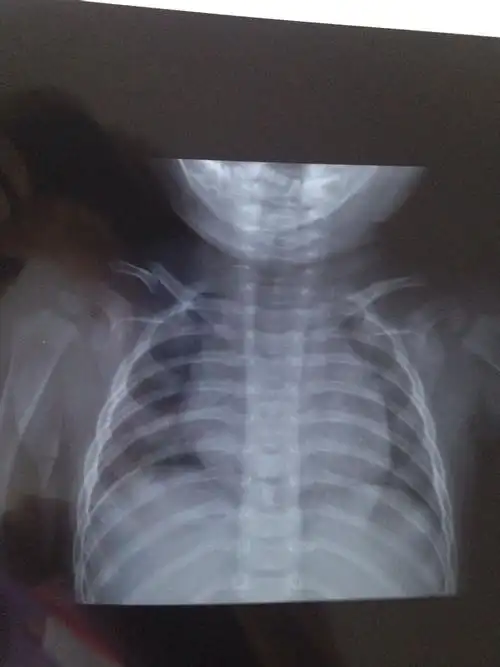

宝宝7个月锁骨骨折了,大夫说不用绷带固定,让自然生长,会有什么影响吗